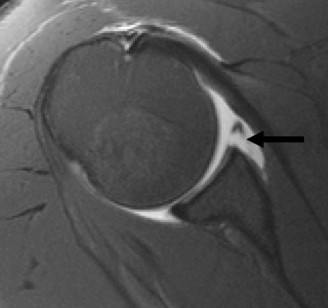

Advanced imaging is mandatory when bone loss is suspected. While Magnetic Resonance Imaging or MR Arthrogram is excellent for evaluating the capsulolabral complex, rotator cuff, and cartilage, three dimensional Computed Tomography is the gold standard for quantifying osseous defects.

The en face view of the glenoid on 3D CT with the humeral head digitally subtracted allows for precise measurement. The "best fit circle" method is commonly utilized. A circle is drawn matching the contour of the inferior and posterior glenoid, and the area or width of the missing anterior bone is calculated relative to the area or diameter of the circle. The Pico method compares the surface area of the injured glenoid to the contralateral normal glenoid, assuming the contralateral shoulder is uninjured. The humeral head must also be evaluated to calculate the glenoid track, measuring the width of the Hill-Sachs lesion and the intact anterior glenoid bone bridge.